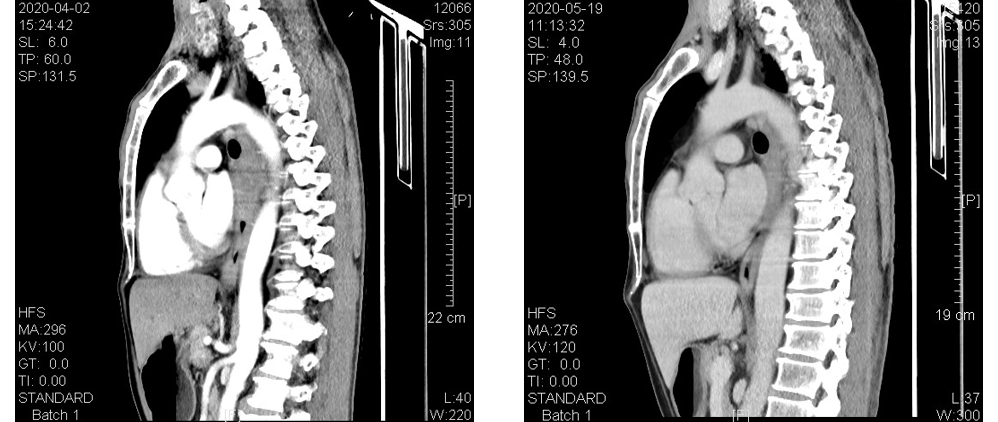

疗效对比(左:4月2日CT结果,右:5月19日CT结果):

食管CT(基线)示:胸中下段食管壁不规则增厚形成肿块,增强后见强化,最厚处约为1.7cm,长约13.4cm,上抵T4水平,下达T9下缘水平,病变段食管与降主动脉间的脂肪间隙消失,与其周长的接触面约为三分之一,向前压迫心包后缘,向左前紧贴左主支气管后壁,后壁略弧形受压改变,向右与奇静脉间的境界不清。

2、2020年5月28日:相关检查无手术禁忌症后在全麻下行“胸腔镜食管癌三野根治术+空肠造口术”。术顺,术后患者恢复好。

术后病理示:(食管胸中段)病变处粘膜糜烂坏死,肉芽组织增生,管壁全层大量慢性炎症细胞、泡沫细胞及多核巨细胞反应,未见明显肿瘤残留,符合重度治疗后反应。